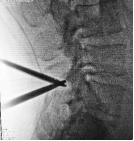

3.微创PKP技术:老年压缩性骨折球囊扩张椎体成形术

经皮球囊扩张椎体后凸成形术是皇冠娱乐城

很早就开展的一项微创技术,已经有20多年,每年手术约200例,尤其适用于老年骨质疏松引起的胸腰椎骨折;椎体转移性肿瘤(溶骨性破坏);引起疼痛症状的椎体血管瘤、多发性骨髓瘤、Kummell 症。局部麻醉,创伤小恢复快,第二天可以下床活动,迄今为止最高手术患者92岁高龄。